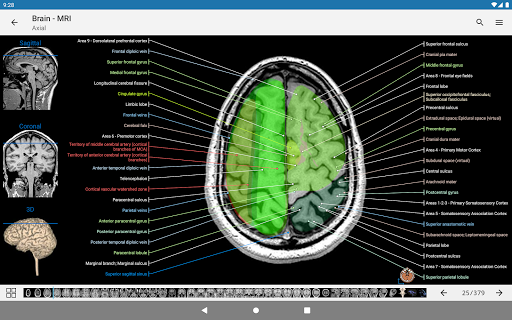

e-Anatomy tiene más de 26 000 imágenes que contienen series de imágenes en vistas axiales, coronales y sagitales, así como radiografías, angiografías, imágenes de disección, gráficos anatómicos e ilustraciones. Todas las imágenes médicas fueron etiquetadas cuidadosamente, más de 967 000 etiquetas disponibles en 12 idiomas, incluida la Terminologia Anatomica latina.

- Desplácese por los conjuntos de imágenes arrastrando el dedo

- Acerque y aleje el zoom

- Toque las etiquetas para mostrar las estructuras anatómicas

- Seleccione las etiquetas anatómicas por categoría

-Un pictograma ahora está presente en cada imagen y representa la orientación actual del cuerpo

- La vista anatómica ahora muestra más etiquetas